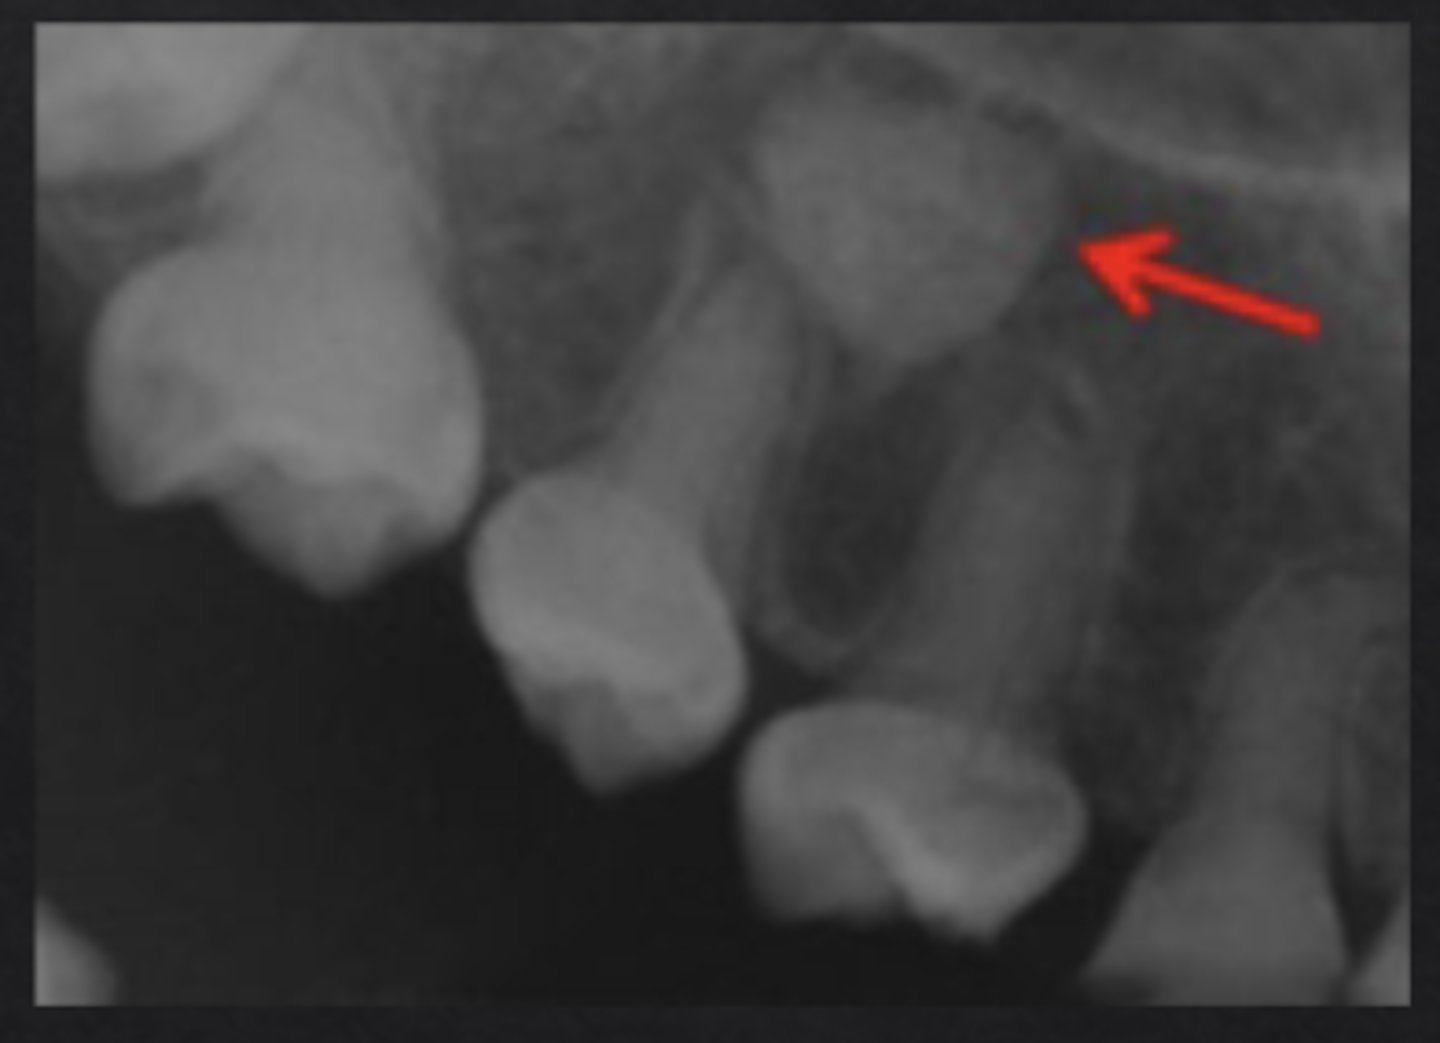

What is idiopathic osteosclerosis?

"Dense bone island" an area where normal trabecular bone is replaced with dense cortical bone

How does idiopathic osteosclerosis appear radiographically?

Region of dense radiopaque bone, blends with surrounding bone

Does idiopathic osteosclerosis typically affect adjacent structures?

No